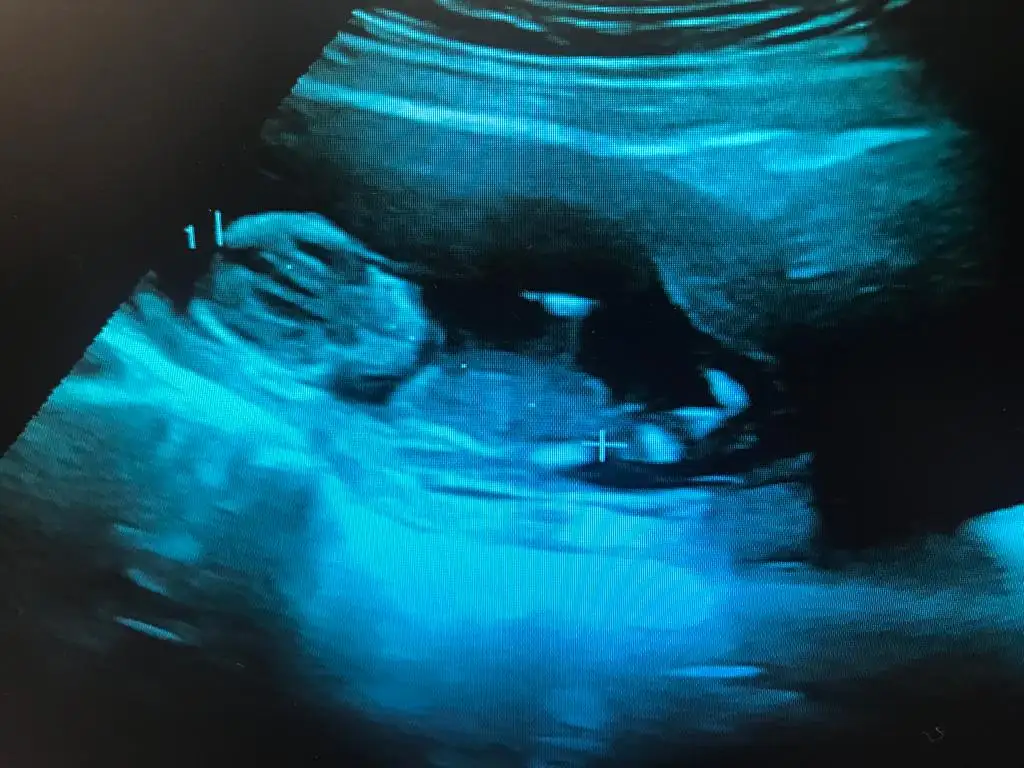

kız görünüyor canımBenimkinide bakar mısınız 10+3 karın ultrason. :)

Erkek canım :) geçtiğimiz hafta öğrendim. Doğru tahmin ediyormusun diye bi kontrol edeyim dedim olmadı maalesef :)kız görünüyor canım![]()

hay maşallahErkek canım :) geçtiğimiz hafta öğrendim. Doğru tahmin ediyormusun diye bi kontrol edeyim dedim olmadı maalesef :)

Allah razı olsunhay maşallahşaşırmadım değil çünkü arada kaldığım bir görüntü de değildi

Allah sağlıcakla kucağınıza aldırsın umarım değişmez